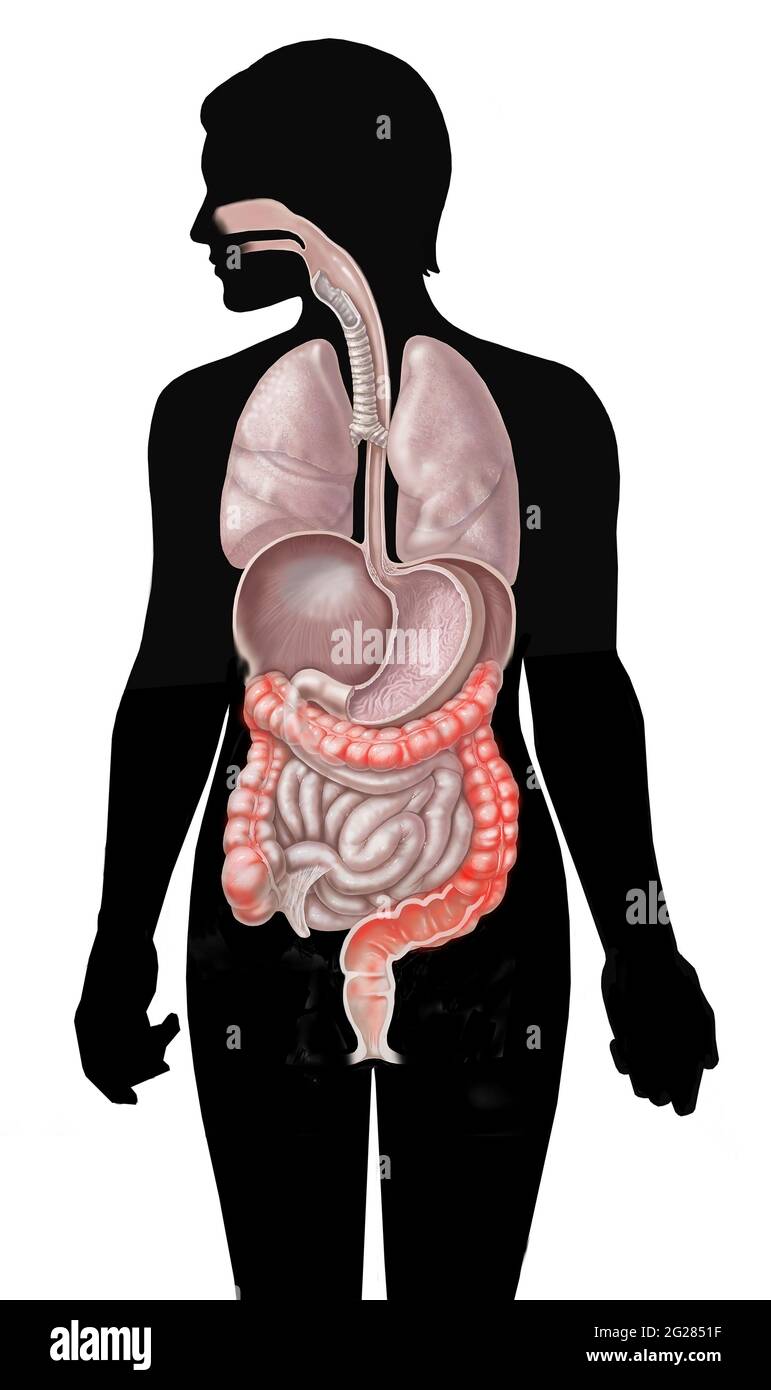

Emplacement de la colite ulcéreuse dans le gros intestin sur la silhouette de la femme. Banque D'Imageshttps://www.alamyimages.fr/image-license-details/?v=1https://www.alamyimages.fr/emplacement-de-la-colite-ulcereuse-dans-le-gros-intestin-sur-la-silhouette-de-la-femme-image431668091.html

Emplacement de la colite ulcéreuse dans le gros intestin sur la silhouette de la femme. Banque D'Imageshttps://www.alamyimages.fr/image-license-details/?v=1https://www.alamyimages.fr/emplacement-de-la-colite-ulcereuse-dans-le-gros-intestin-sur-la-silhouette-de-la-femme-image431668091.htmlRM2G2851F–Emplacement de la colite ulcéreuse dans le gros intestin sur la silhouette de la femme.